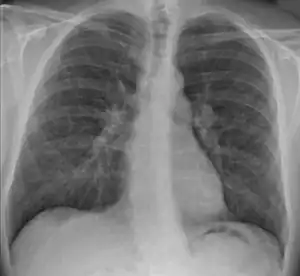

Chest X-ray showing the typical nodularity of sarcoidosis, predominantly in the bases of the lungs.